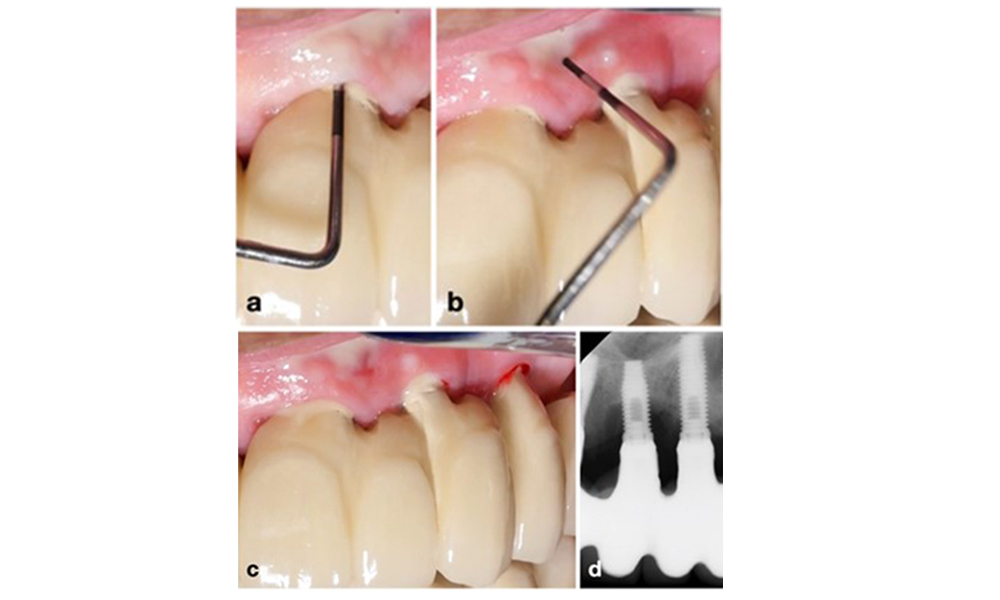

Finally, it has been observed, that implants with less than 2 mm of keratinised mucosa exhibit an increased prevalence of peri-implantitis, and higher plaque accumulation and bleeding indices (Ramanauskaite et al. 2022). This highlights the importance of considering keratinised mucosa augmentation in peri-implantitis prevention and management (figure 14).

An implant lacking keratinised mucosa at the buccal aspect (a). To increase the width of the keratinised mucosa, a gingival graft was placed (b), enhancing oral hygiene effectiveness (c).